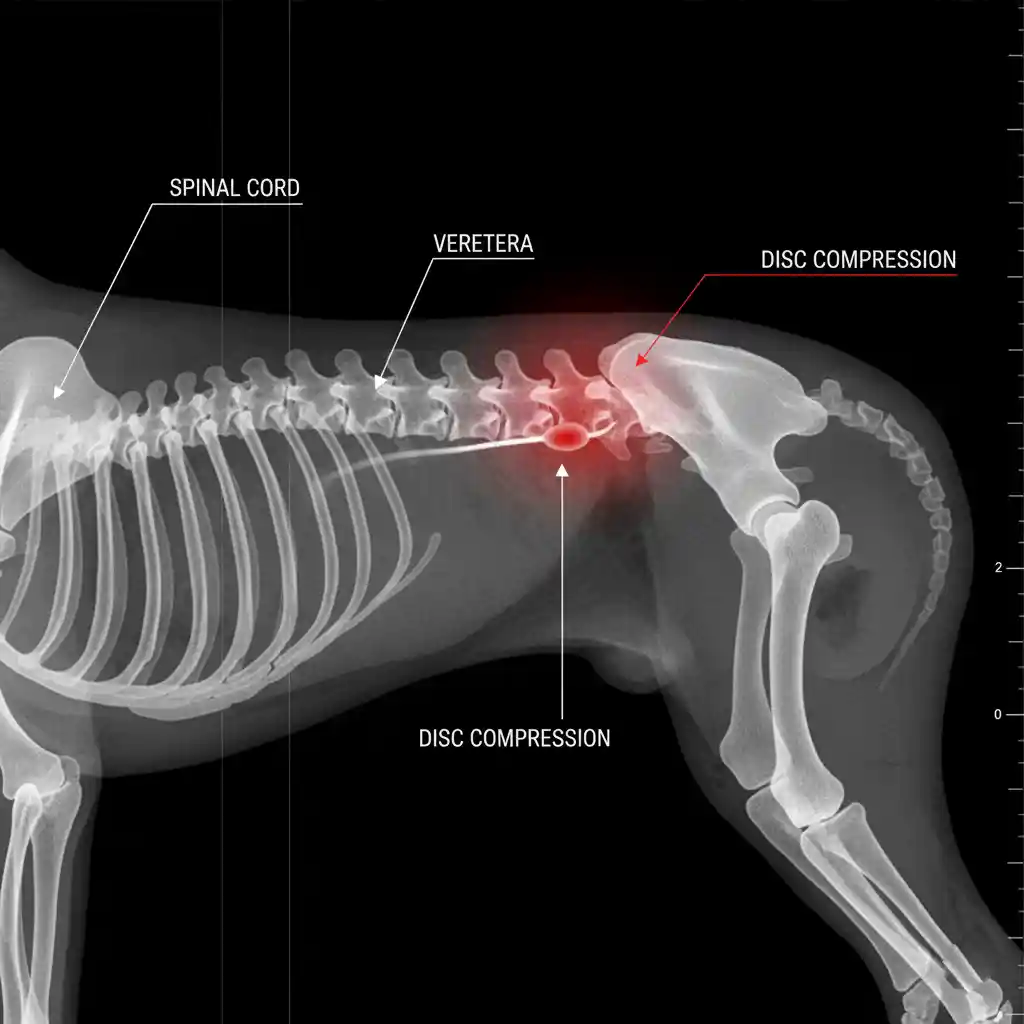

Medical Disclaimer: The information provided in this article is for educational purposes only and does not substitute professional veterinary advice. Always consult your veterinarian if your pet is showing signs of distress. Have you ever heard the phrase, “Better safe than sorry”? It’s never more true than when it comes to your furry friend’s health. […]